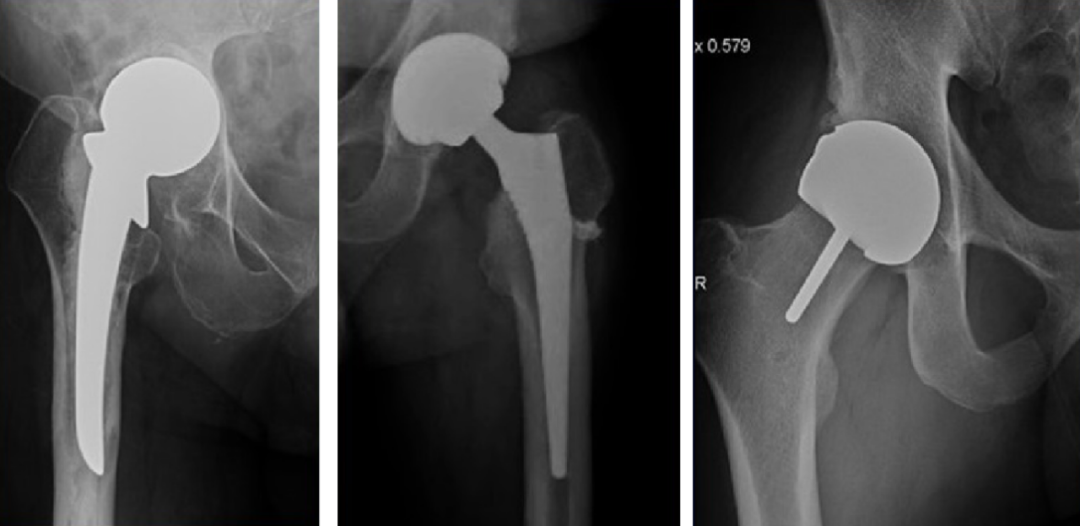

一般包括全髋关节置换术及半髋关节置换术:

从左至右分别为半髋关节置换、全髋关节置换、髋关节表面置换